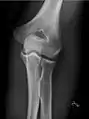

• Elbow - AP and Lateral. Radial head projections available on request

• Knee - AP and Lateral. Intra Condular projections on request